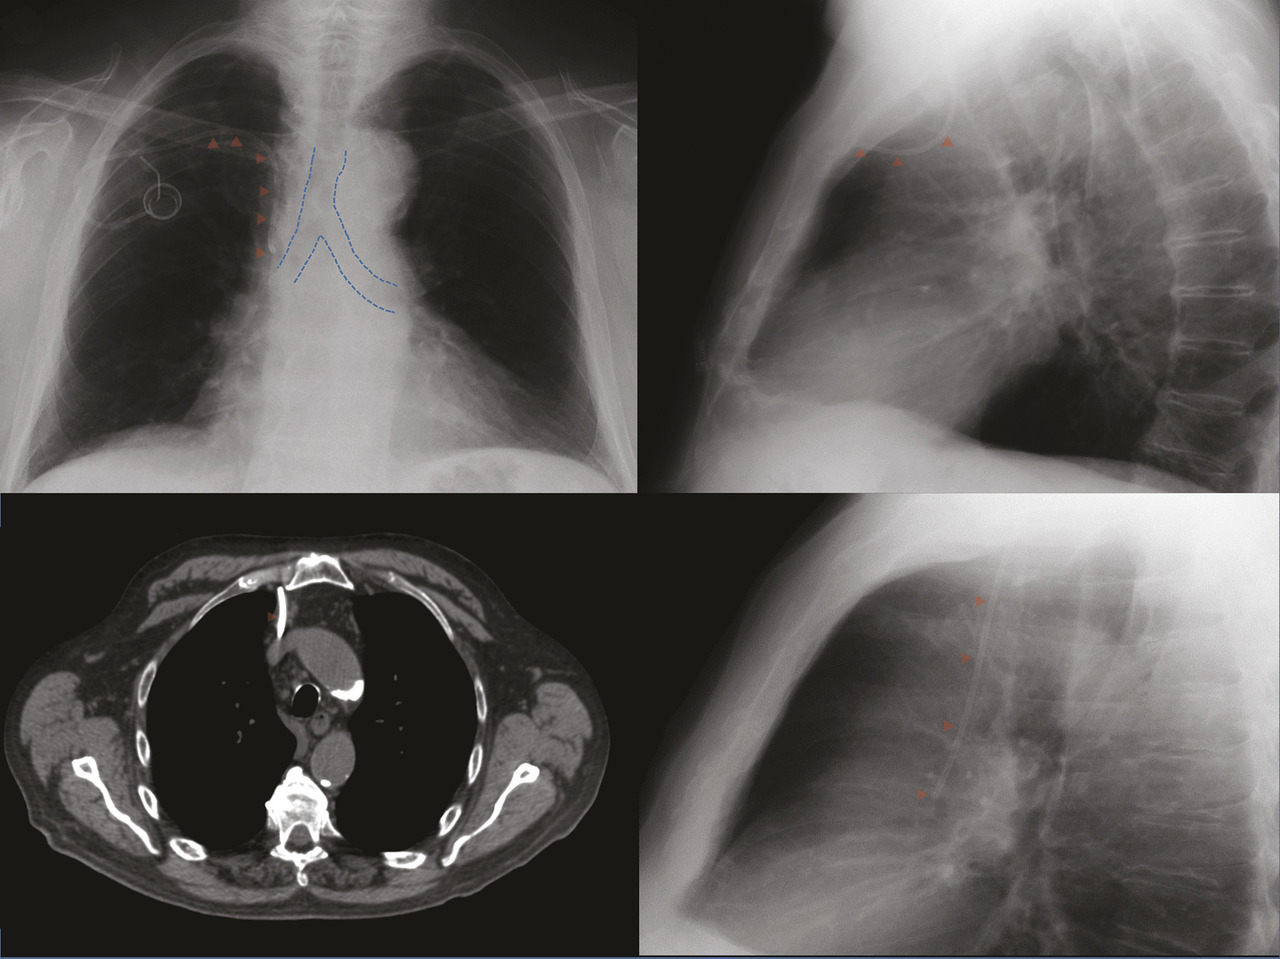

Chez ce patient, une radiographie de thorax était demandée pour contrôler la position d’un cathéter veineux central avec chambre implantable. Sur le cliché de face (fig. 1A ), l’extrémité distale du cathéter pouvait sembler correctement positionnée, mais le cliché de profil (fig. 1B ) montrait une anomalie évidente de trajectoire. La tomodensitométrie (fig. 2 ) confirmait la malposition du cathéter au sein du médiastin antérieur. Pour exemple, la figure 3 montre le trajet d’un cathéter vertical normal vu de profil. Cet exemple montre l’intérêt d’un cliché de profil systématique lors du contrôle de la position d’un cathéter.

La position idéale de l’extrémité distale des cathéters veineux centraux reste controversée. La pointe du cathéter est le plus souvent posi-tionnée dans la portion moyenne de la veine cave supérieure, en dehors du repli péricardique enveloppant la partie basse de cette veine, ce qui correspond à peu près au niveau de la carène, cela afin de prévenir une tamponnade cardiaque en cas de blessure vasculaire.1 il faut cependant éviter une terminaison trop crâniale du cathéter, qui accroît le risque de thrombose.2